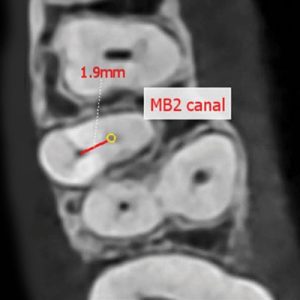

3D snimanje zuba omogućava detaljan uvid za širok spektar stomatoloških procedura.

Uz 3D ENDO dobijate precizno 3D snimanje zuba za usko definisane željenje regije.